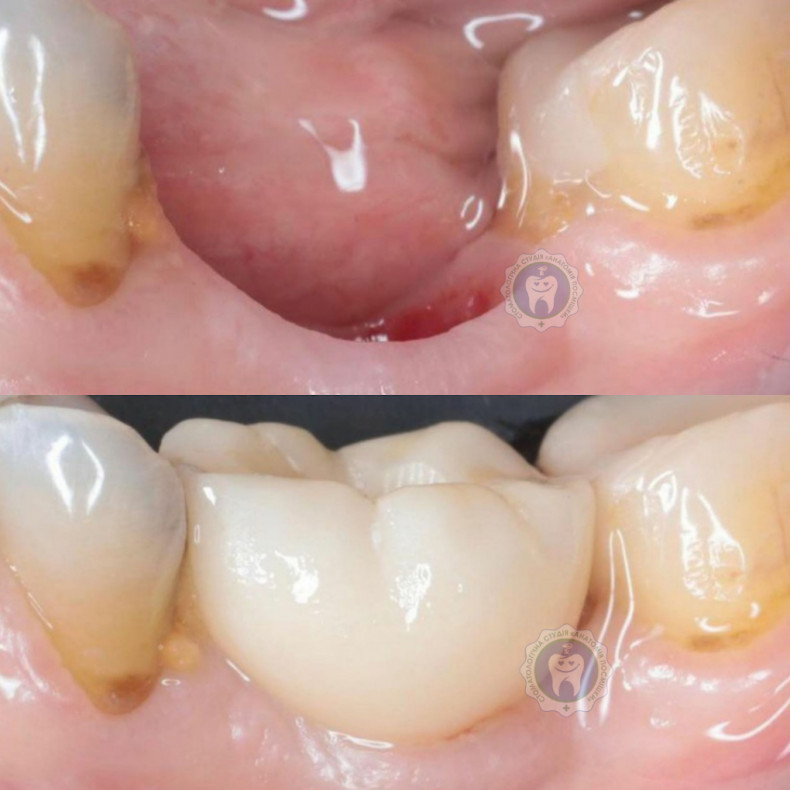

Професійне чищення зубів — це гігієнічна процедура, спрямована на видалення нальоту, каменю та запобігання захворюванням ясен. Нижче наведені пропозиції від клінік і фахівців, які виконують професійне чищення в умовах кабінету.